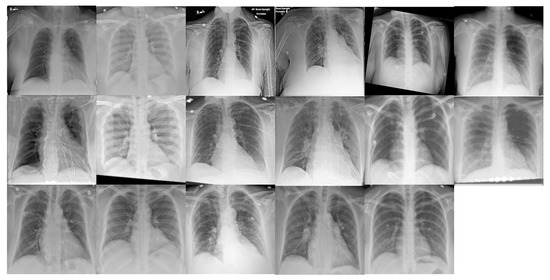

4.1. Database